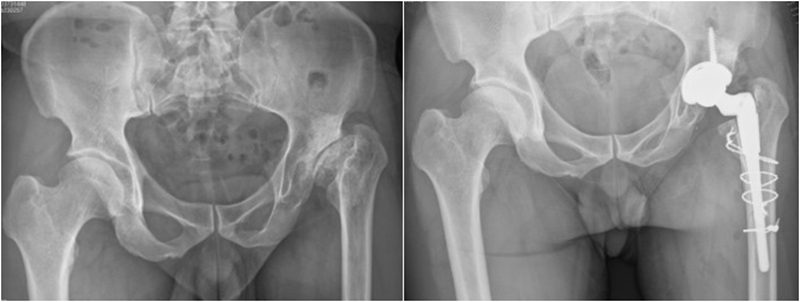

Ⅲ、干骺端畸形

硬化骨、骨赘、骨质疏松、髓腔宽大

转子间骨折畸形愈合后常导致干骺端畸形,干骺端遗留大量硬化骨或髓腔成角,术中需在确认髓腔开口位置后,首选用小骨刀或高速磨钻去除硬化骨,打通髓腔。

干骺端畸形还可引起髓腔增宽,骨量减少,骨质疏松,不能为近端压配固定型的假体提供良好稳定。宜选用全微孔涂层远端固定假体。

Ⅳ、股骨干畸形

(1)前倾异常增大

先股骨侧操作,根据联合前倾角及各向稳定性决定髋臼前倾,以达最佳稳定。

(2)髓腔狭小

细长股骨柄与狭窄髓腔匹配。